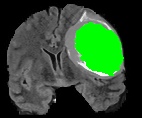

We present results obtained on the MICCAI multi-modal Brain Tumor Segmentation (BRATS) dataset [49]. This challenging dataset contains real and simulated patient data, with overall poor resolution and large variation of tumor shape and position. For both types, high grade (HG) and low grade (LG) tumors are provided with four modalities: T1, contrast enhanced T1 (T1C), T2, and FLAIR. Overall, there are 20 and 10 real patient data with respectively HG and LG tumors, and 25 images for both HG and LG simulated tumor data. We use the same SPM parameters as in Section V-B, taking a multi-modal histogram, containing the levels of gray intensity on all MRI modalities as descriptor for superpatch matching, and performing the regularization (8) at the pixel scale to compare with pixel-wise ground truths. Each subject is segmented by the remaining of its type in a leave-one-out procedure.

In Fig. 12, we show several tumor segmentation results for all data types.

In Table II, we compare results obtained using different descriptor structures:

patch-based [48], superpixel-based [54],

and superpatch-based (= pixels).

We use the Dice coefficient [55] as evaluation metric,

measuring the overlap between the automatically segmented structure and the ground truth.

The superpixel-based approach

appears very limited since it fails at capturing the tumor context and their location in other images.

Regular patches are also limited in this context, due to the variations in the structure shapes.

Superpatches provide a robust descriptor, since they follow image intensities and capture the superpixel neighborhood,

leading to more accurate segmentation.

These experiments demonstrate that superpatches within the SPM framework provide fast and accurate segmentation results

even on non-registered multi-modal images with poor resolution.